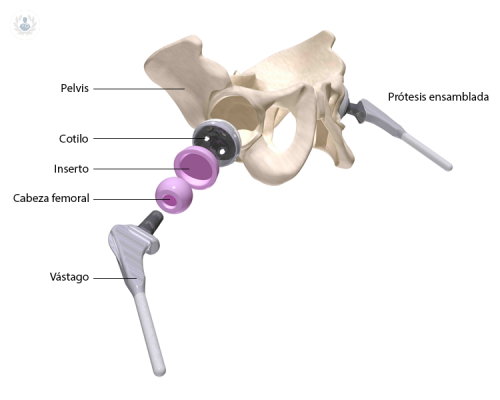

Reemplazo de cadera: conoce todo sobre esta cirugía

La artrosis de cadera es un padecimiento crónico y para el tratamiento de casos muy avanzados se puede indicar el reemplazo de cadera. Se trata de un procedimiento quirúrgico extremadamente reglado y estandarizado, el cual debe ser realizado por un equipo de especialistas para garantizar los mejores resultados. Conozca los detalles sobre esta intervención